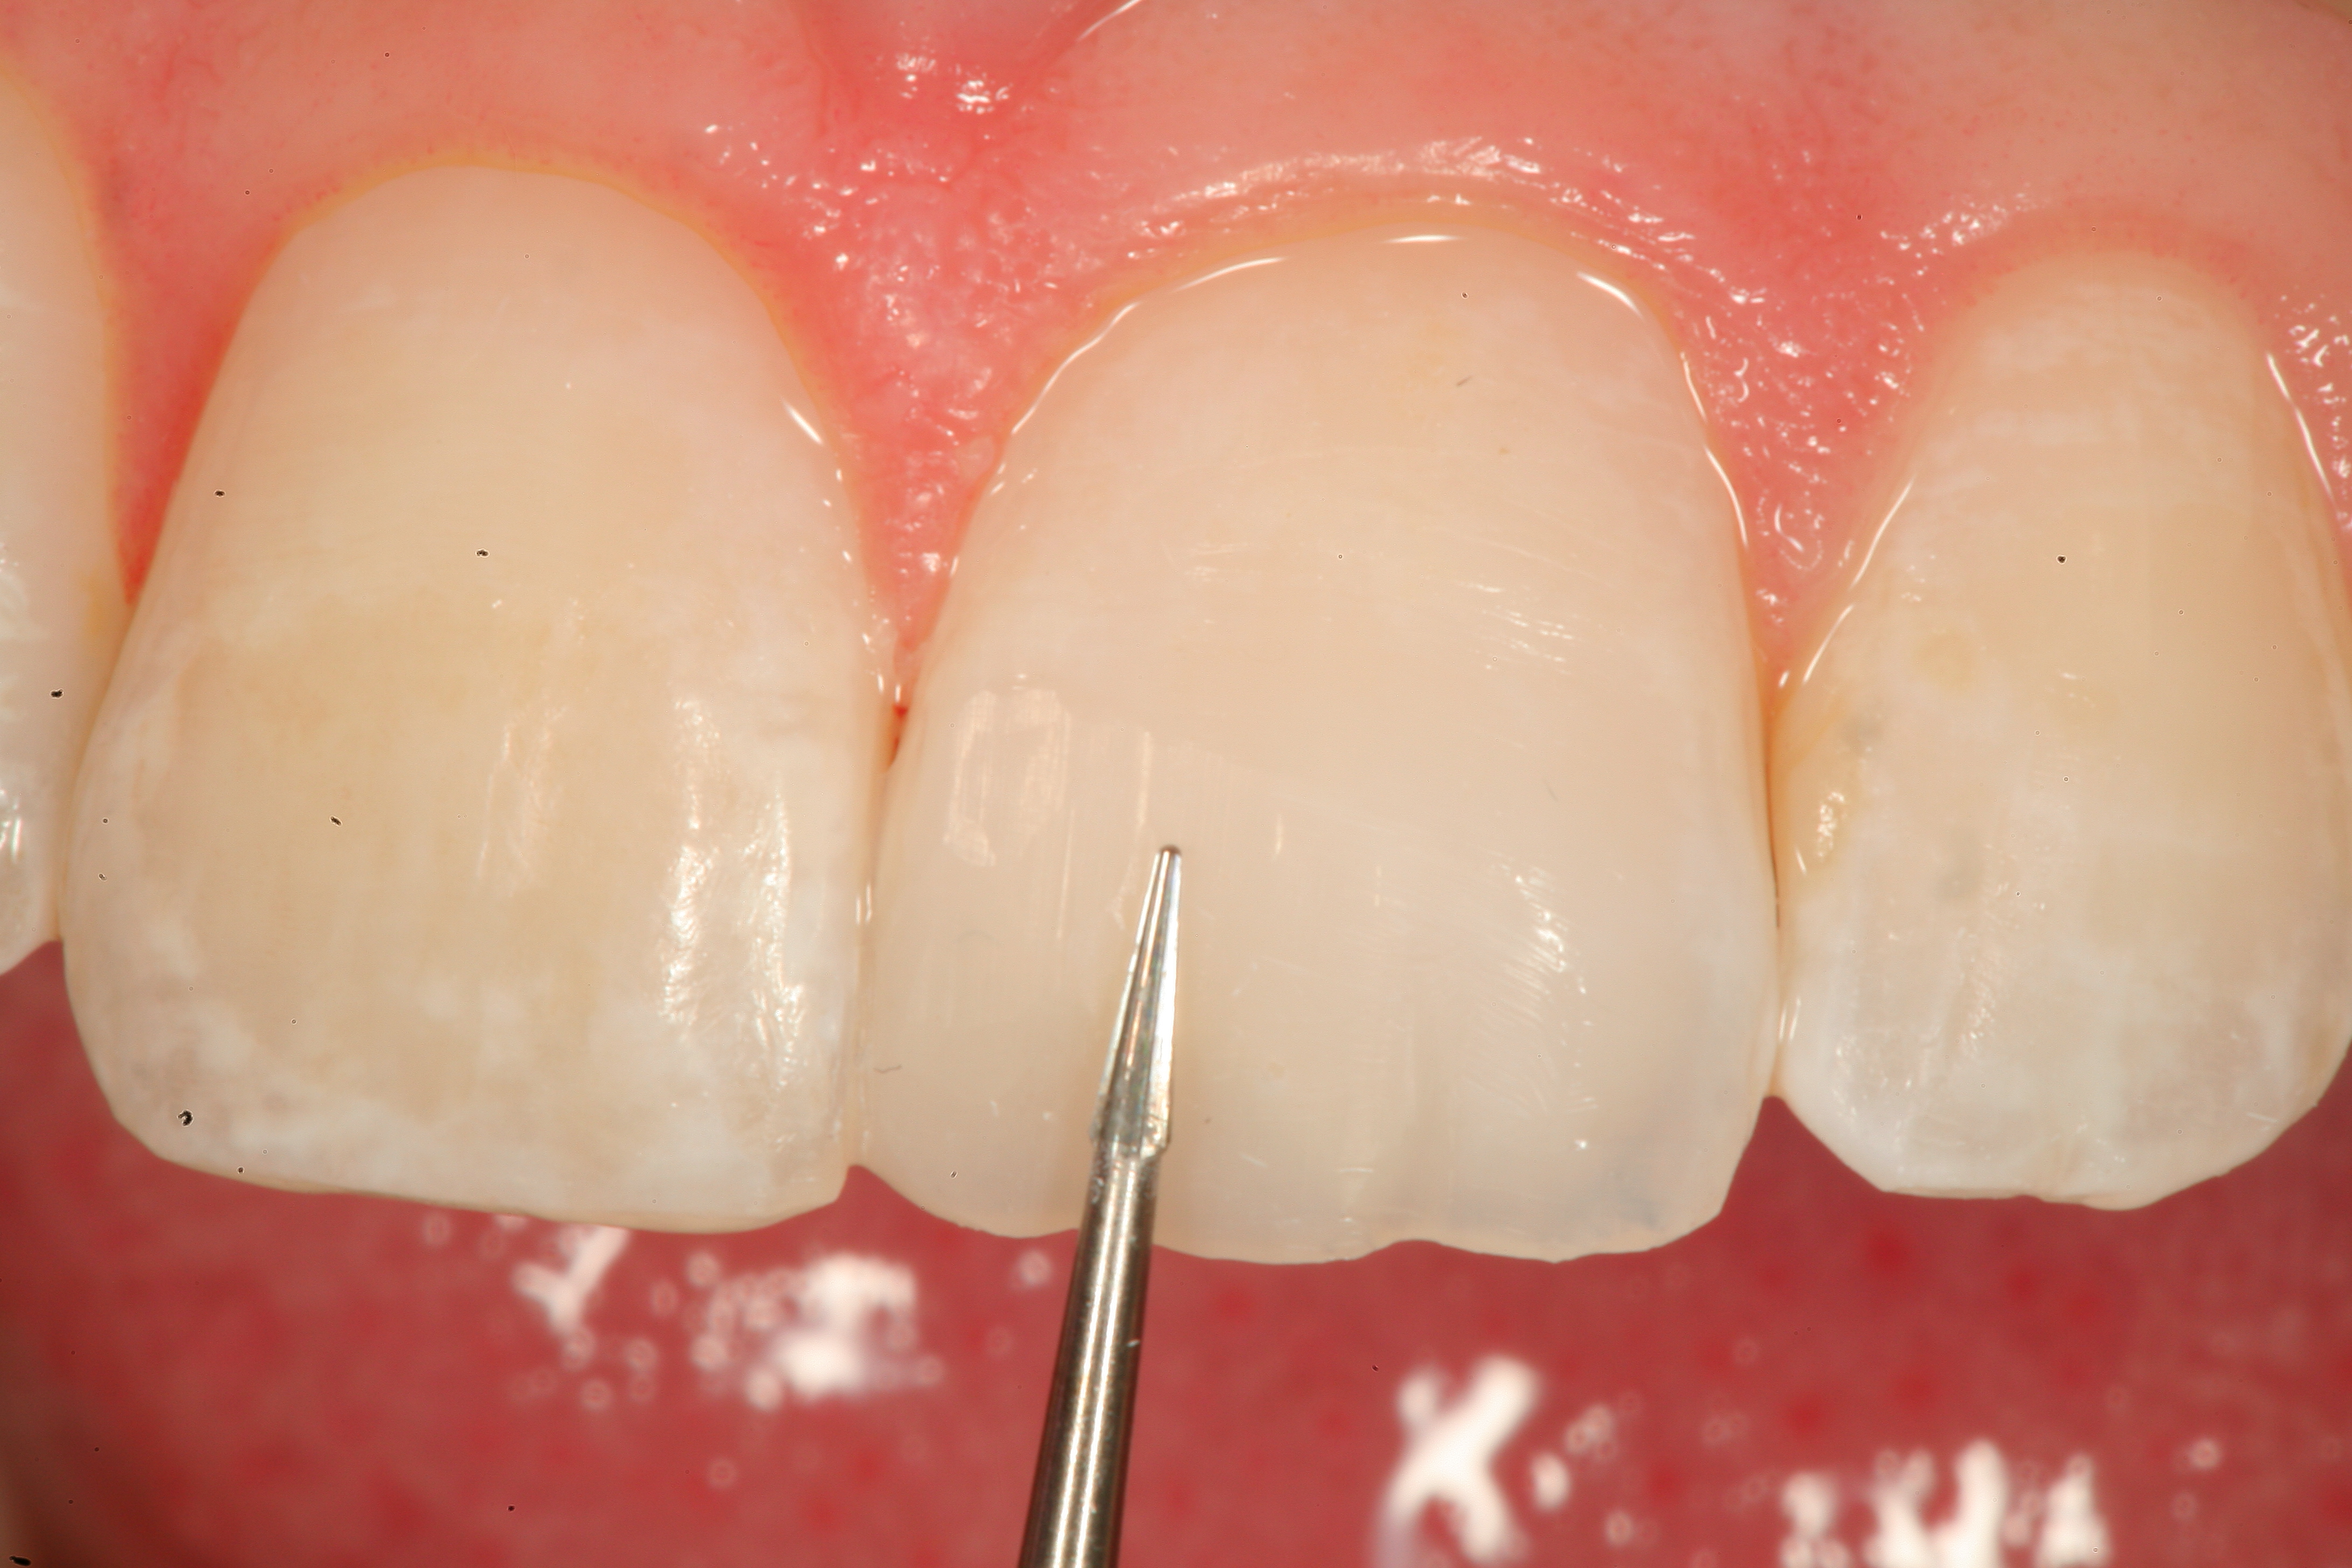

Fig 19. The completed Class IV Giomer restoration is seen on tooth No. 9 from the facial aspect. Note the esthetic quality of this layered anterior composite restoration as it compares with the surrounding natural teeth.

Figure 19